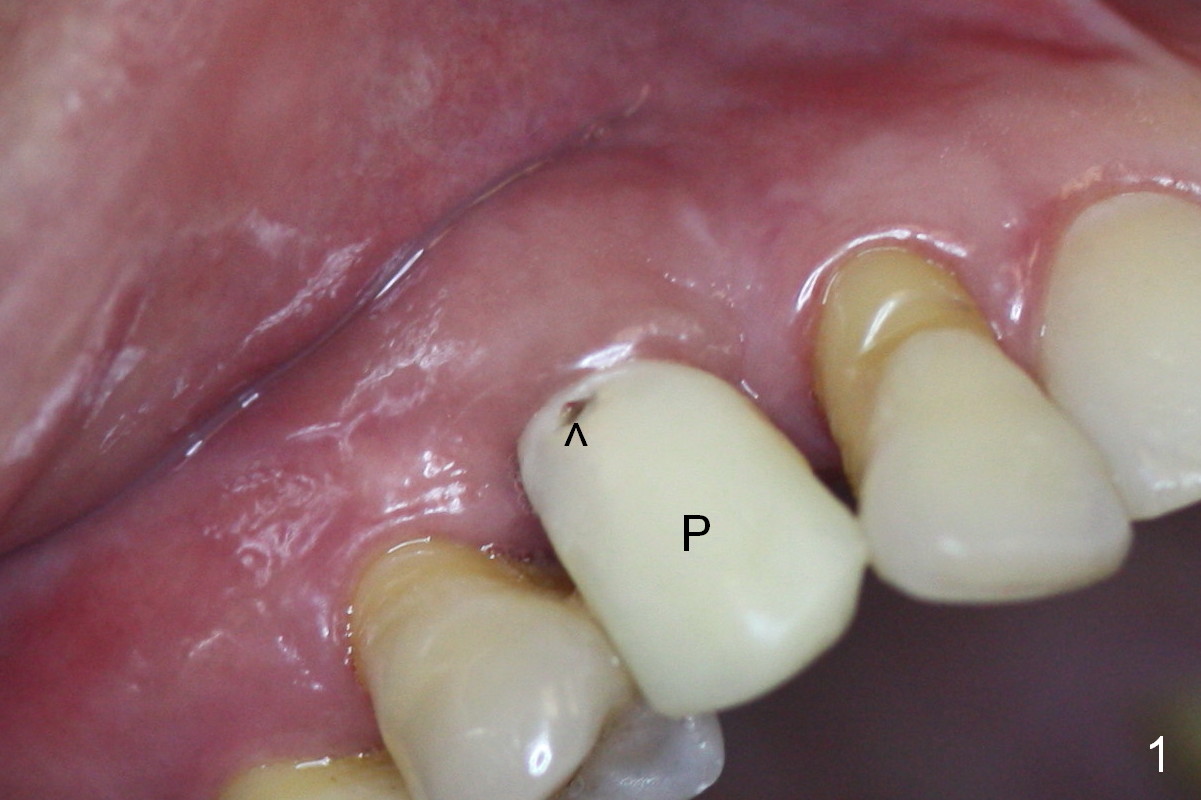

Four months post implant placement, the immediate provisional (Fig.1 P) has mobility with tenderness and perforation at the cervix (^). When the provisional is removed, the buccal plate bulging is more evident (Fig.2 arrowheads). The latter is apparently caused by bone expansion associated with implant placement (Fig.3 black *), since the bulging is not so obvious in a preop CBCT 3 D image (Fig.4 *). There is a layer of fiber granulation tissue (Fig.3 white *) around the mobile implant (I). More fiber tissue is noted when the implant is removed (Fig.5). A new osteotomy is created in the palatal wall of the existing implant site with 2 mm pilot drill, followed by 2.5 and 3 mm reamers. As a 4.5x17 mm tap is being inserted (Fig.6 T), it is deviated buccally. Reamers are re-used to try to remove more palatal bone to let the implant be placed more palatally. When a 4.5x17 mm tissue-level implant is placed (Fig.7,8 I with insertion torque >60 Ncm), there is a small buccal gap (Fig.8 *). A 20° angled abutment (Fig.7,8 A) is placed. An immediate provisional is fabricated with cosmetic satisfaction.